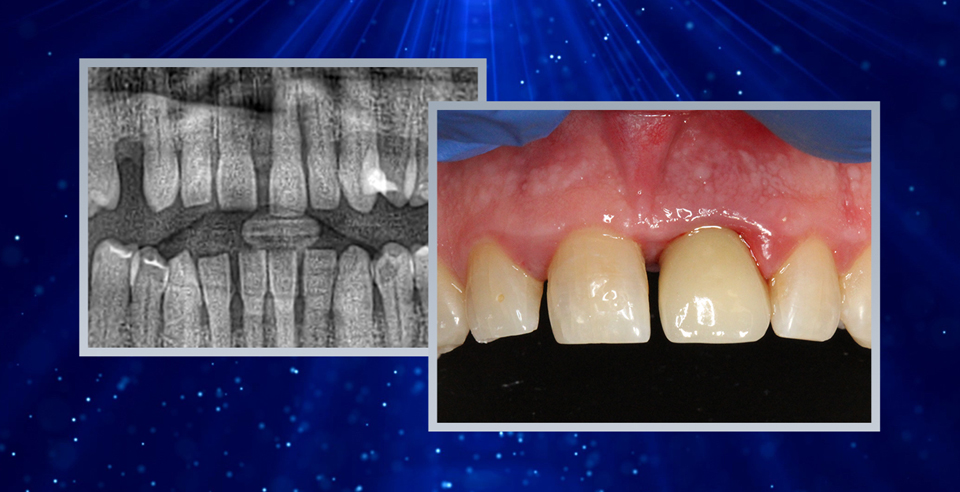

MAXILLARY CENTRAL INCISORS REPLACEMENT USING PET - CASE BY DR CARMY MICHAEL